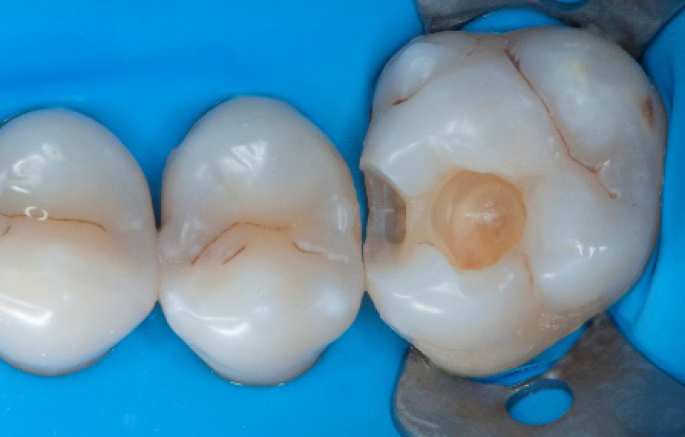

Before

Initial situation: an old class I composite restoration on 1.6. New caries on the mesial wall. Presence of plaque and inflammation.